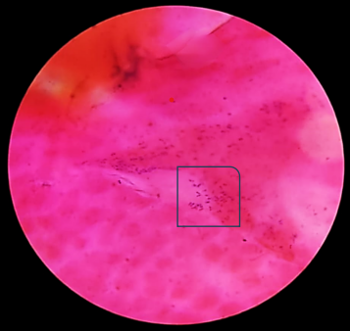

Slit lamp

examination was performed in both patients which

revealed coarse, raised punctate epithelial

lesions with a typical stuck on appearance

[Fig-2].

Fig 2: Slit lamp

examination revealing typical stuck on

appearance |